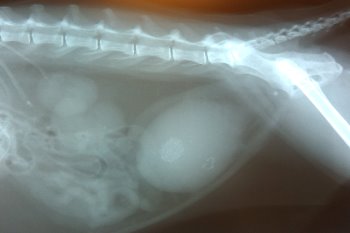

X-ray of a cat with numerous bladder stones